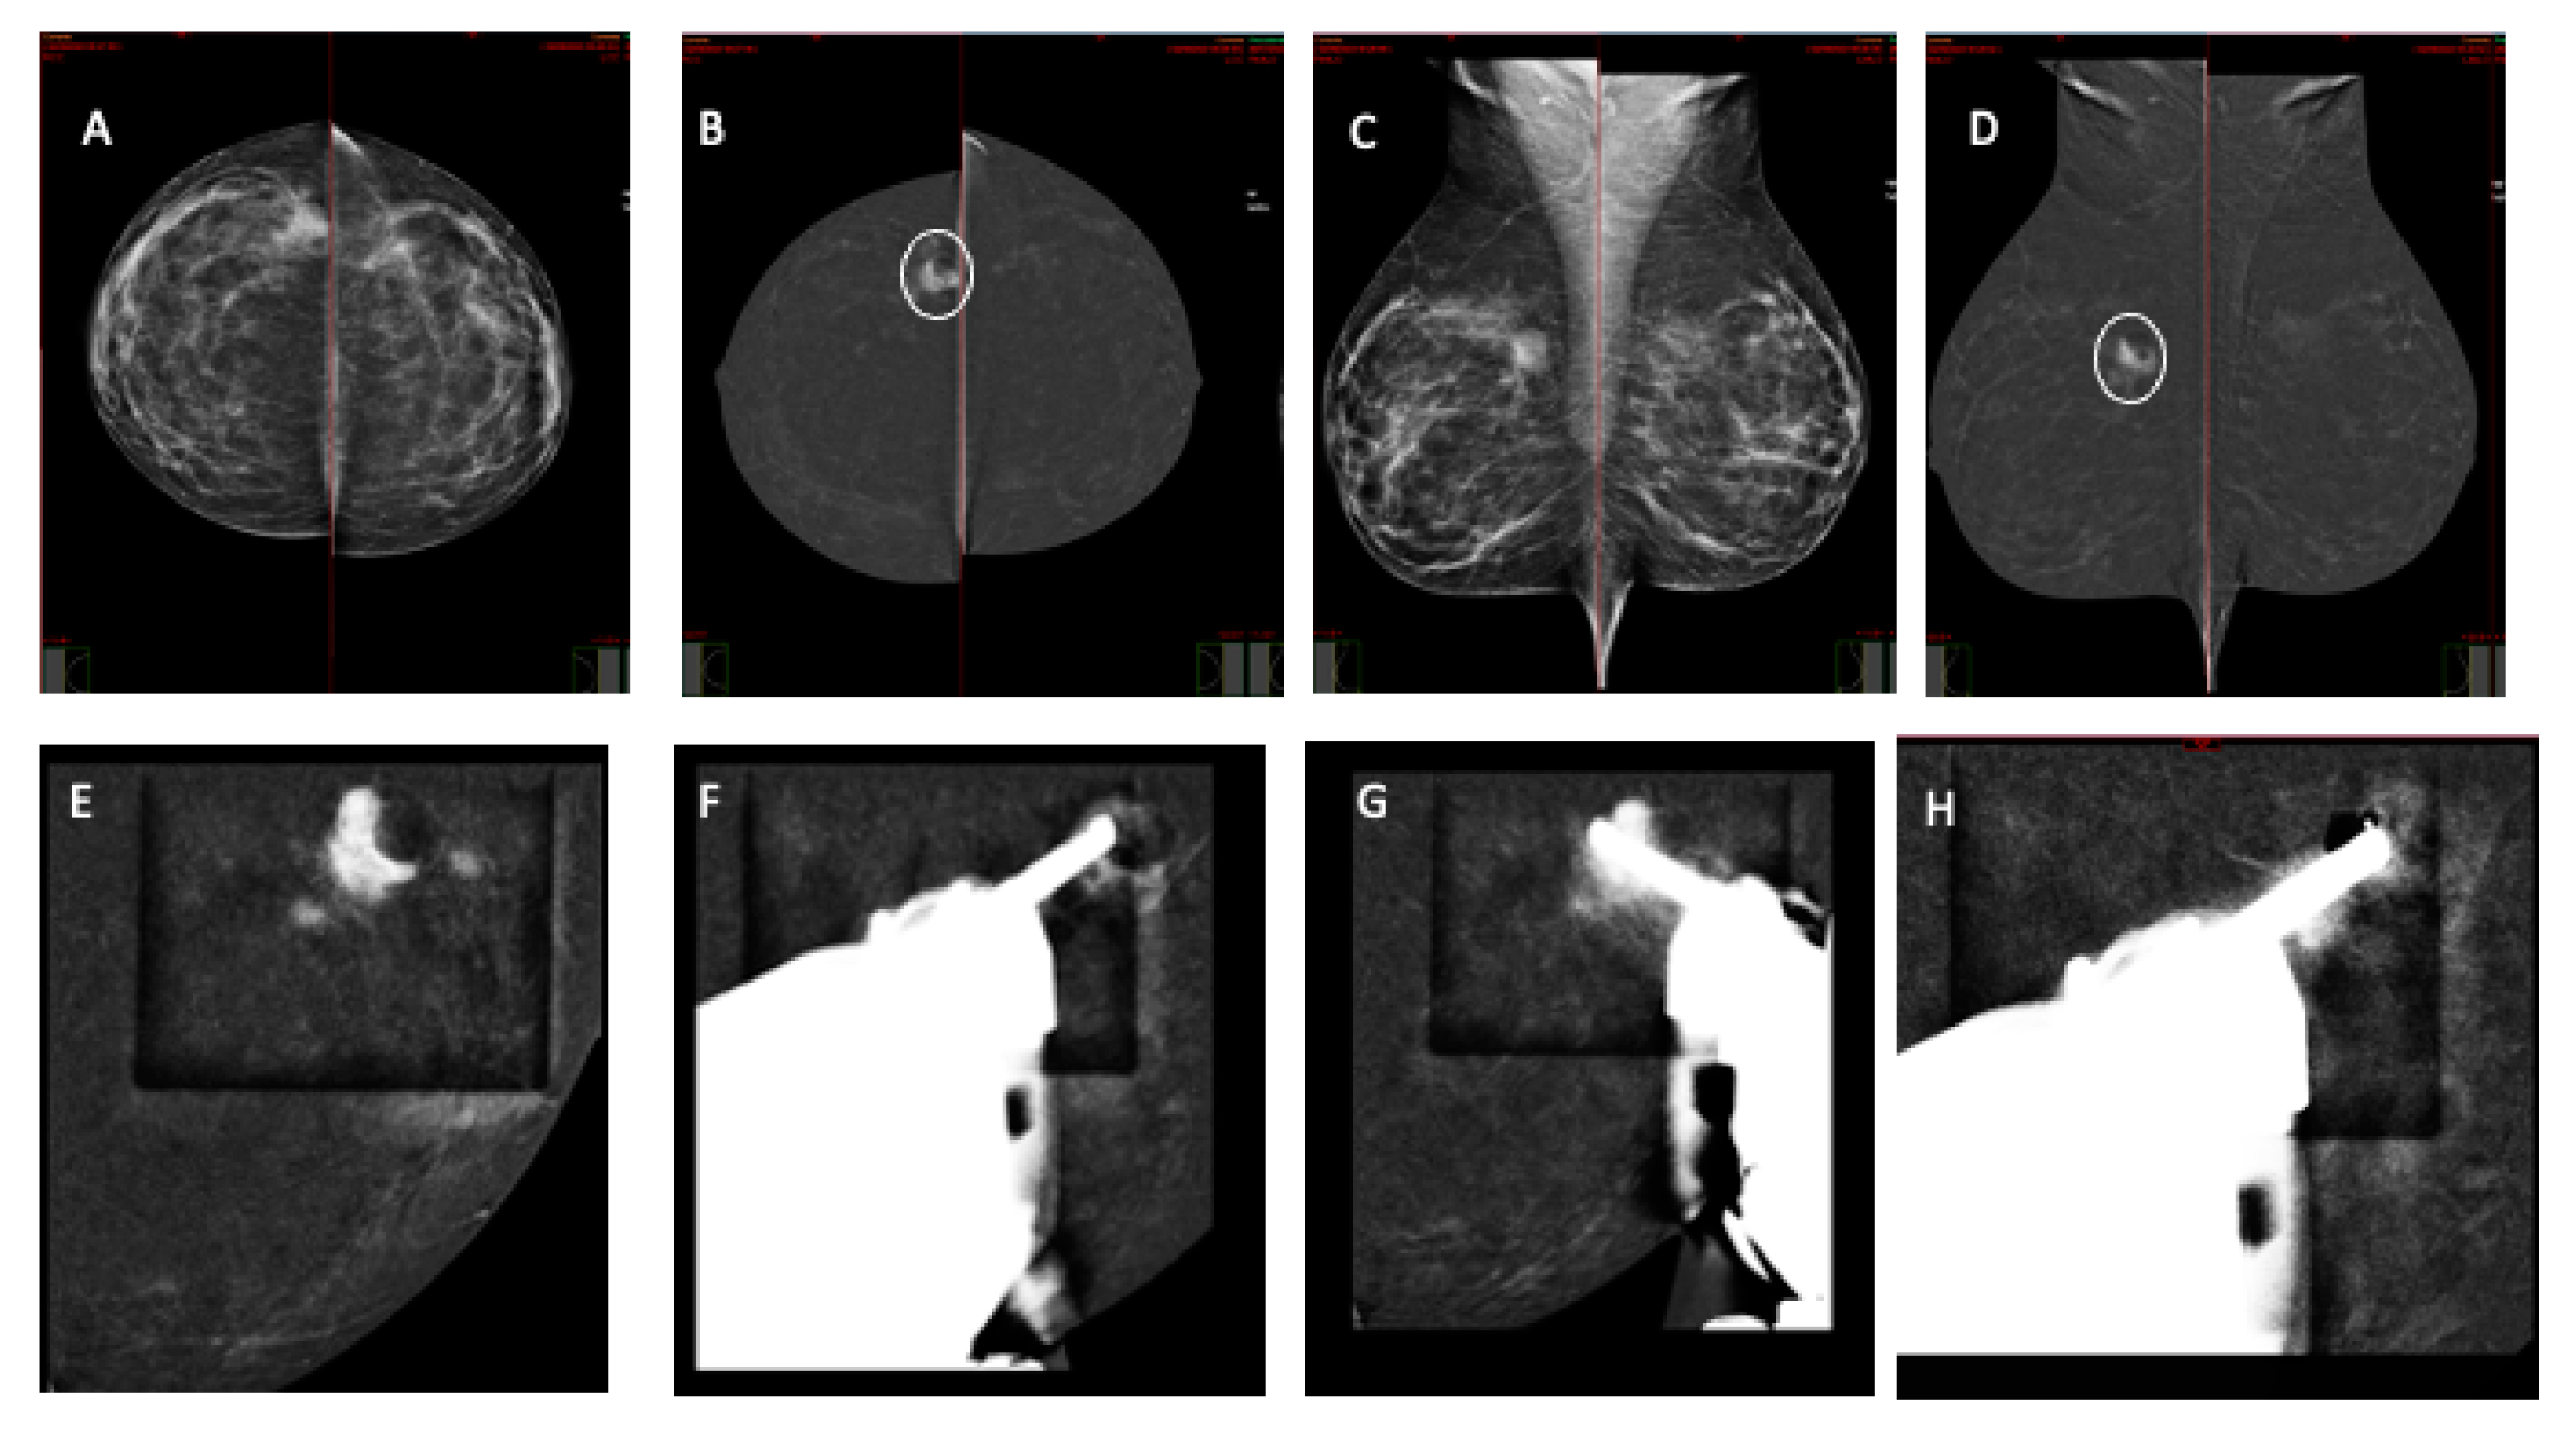

2.3. CEM-Guided Breast Biopsy Procedure